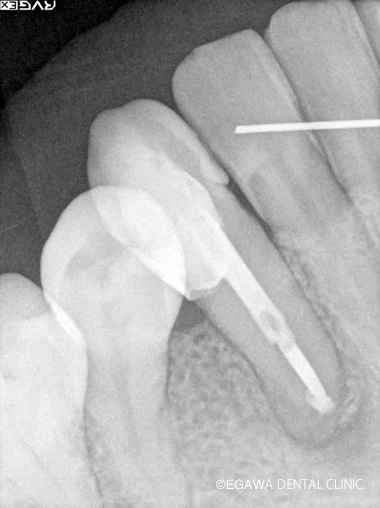

症例3

術前

術中

術後